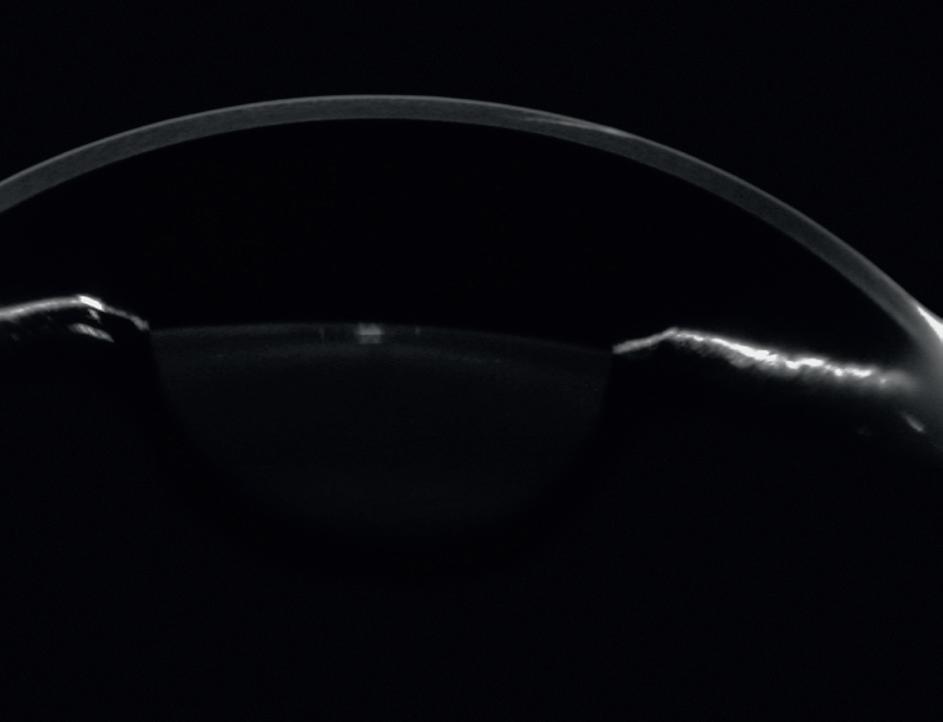

Discover the power of CASIA2 through real-world cases provided by eye care professionals like you. In this brochure, we proudly present a collection of diverse patient experiences that showcase the versatility and clinical utility of CASIA2 Cornea / Anterior Segment OCT.

Dive into the insights, outcomes, and lessons learned from these cases. See firsthand how CASIA2 is transforming ophthalmic care.